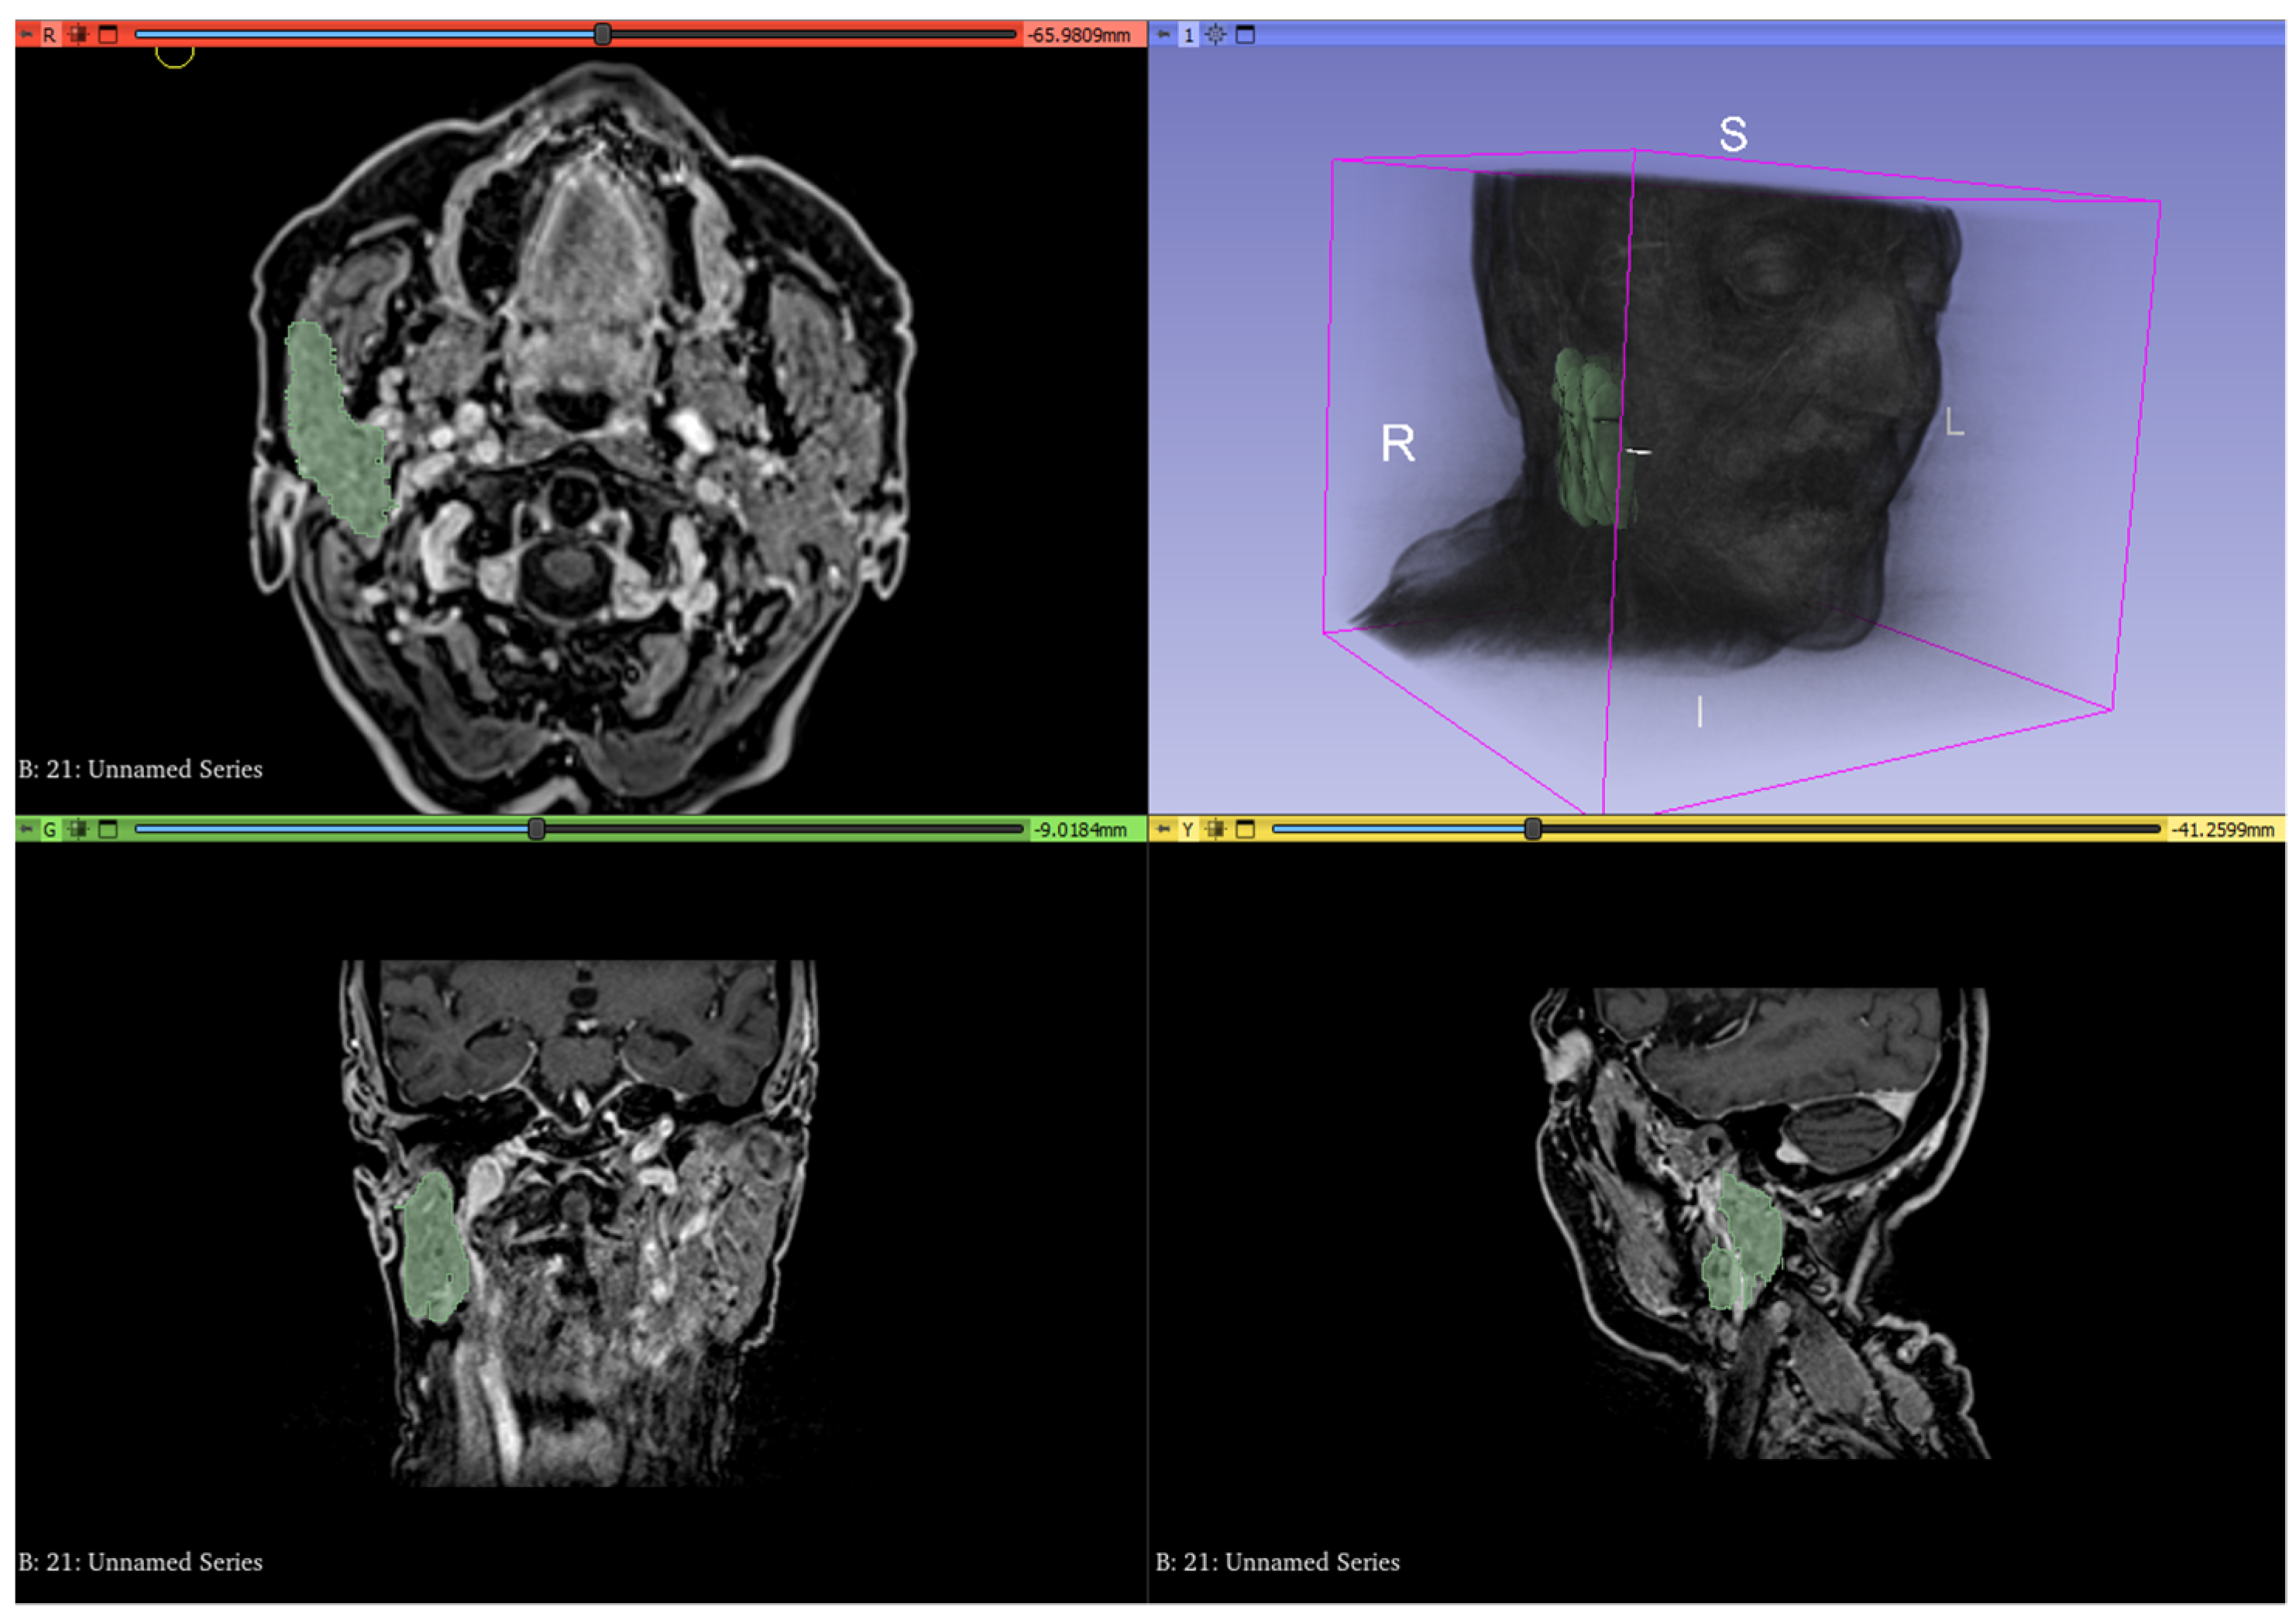

2.4. Texture Analysis

The MRI images obtained with T1 post-contrast sequences and the ADC maps before and after RT were imported into 3D slicer (www.3dslicer.org (accessed on 12 February 2022)) v10.4.2 software. The parotid and submandibular glands located on the same side of the oropharyngeal cancer, corresponding to the irradiated side, were segmented for the entirety of their volumes by a radiologist with 3-years’ experience in head and neck cancer using the “segmentation wizard” extension for 3D slicer (Figure 3). Specifically, the segmentation of the gland located on the irradiated side was performed on CE-T1 sequences both before and after RT. The same method was carried out on the ADC maps thus resulting in a total of 4 different segmented volumes per gland. This process resulted in a total number of 216 volumes being segmented with 4 submandibular and 4 parotid gland volumes investigated for each of the 27 patients. Texture features were analyzed and extracted from such volumes using the extension “Pyradiomics” for 3D slicer.

Figure 3. Whole volume segmentation of the right parotid gland using 3D slicer software on contrast-enhanced T1 sequences. The entire process was performed for submandibular and parotid glands of the irradiated side on both pre- and post-RT contrast-enhanced T1 sequences and ADC maps.